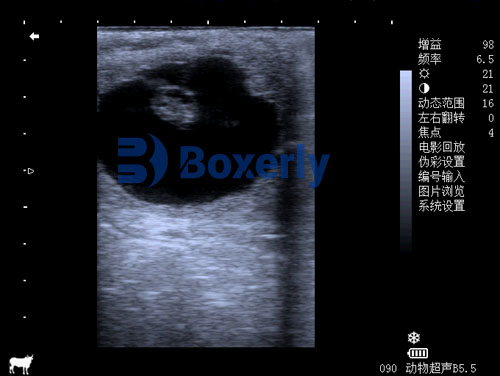

A sonogram refers to the actual image or visual representation produced by an ultrasound examination. In other words, a sonogram is the result of the ultrasound procedure. It is a printed or digital image that shows the internal structures of the body, allowing doctors and medical professionals to assess organs, tissues, or even developing fetuses.

You can think of it like a photograph: the ultrasound is the process that generates the image, and the sonogram is the picture itself.

For example, during pregnancy, a doctor might perform an ultrasound to create a sonogram of the baby in the womb. This sonogram can show the baby’s size, position, and even movements, and can be used to detect any potential issues.